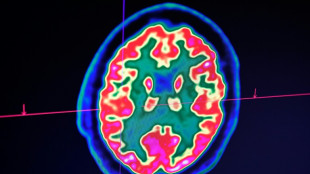

Le cas de la princesse Kate, jeune quadragénaire atteinte d'un cancer, illustre un phénomène d'ampleur. Sans que l'on comprenne bien pourquoi, les moins de 50 ans sont, depuis plusieurs décennies, de plus en plus frappés par cette maladie.